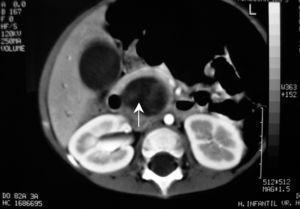

Se realiza una tomografía computarizada (TC) de abdomen que pone de manifiesto una dilatación de la vía biliar intrahepática, visualizándose una imagen redondeada de mayor densidad que la vesícula biliar que desplaza la arteria hepática (fig. 1). La colangiorresonancia realizada mostró una dilatación fusiforme del hepatocolédoco, visualizándose un defecto de repleción intraluminal en el colédoco distal, que ocasiona obstrucción y dilatación retrógrada de la vía biliar (fig. 2).

Figura 2.Colangiorresonancia: dilatación fusiforme del hepatocolédoco, visualizándose un defecto de repleción intraluminal en el colédoco distal, que ocasiona obstrucción y dilatación retrógrada de la vía biliar.